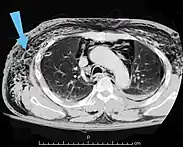

| An abdominal CT scan of a patient with subcutaneous emphysema (arrows) | |

Significant cases of subcutaneous emphysema are easy to diagnose because of the characteristic signs of the condition.[1] In some cases, the signs are subtle, making diagnosis more difficult.[13] Medical imaging is used to diagnose the condition or confirm a diagnosis made using clinical signs. On a chest radiograph, subcutaneous emphysema may be seen as radiolucent striations in the pattern expected from the pectoralis major muscle group. Air in the subcutaneous tissues may interfere with radiography of the chest, potentially obscuring serious conditions such as pneumothorax.[18] It can also reduce the effectiveness of chest ultrasound.[27] On the other hand, since subcutaneous emphysema may become apparent in chest X-rays before a pneumothorax does, its presence may be used to infer that of the latter injury.[13] Subcutaneous emphysema can also be seen in CT scans, with the air pockets appearing as dark areas. CT scanning is so sensitive that it commonly makes it possible to find the exact spot from which air is entering the soft tissues.[13] In 1994, M.T. Macklin and C.C. Macklin published further insights into the pathophysiology of spontaneous Macklin's Syndrome occurring from a severe asthmatic attack.